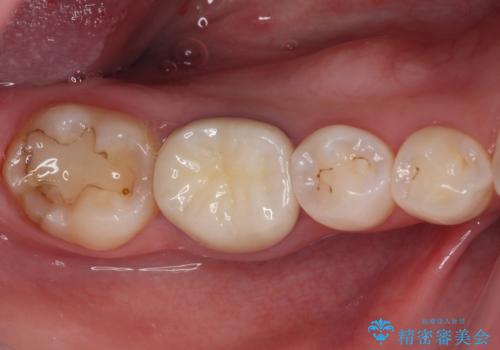

口腔内から、土台も含め銀歯がなくなったことでメタルフリーとなりました。